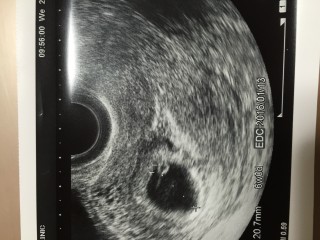

週数は6w4dでしたが、胎嚢の大きさは6w0d相当でした。発育が遅いのかと心配になりましたが、この2週間後に修正が入って、週数は元に戻りました。この時先生に『卵黄嚢がきれいに見えてますね』と言われてとても嬉しかったです。この時は胎芽も心拍も確認できなかったけど、2週間前は胎嚢しか見えなかったところに卵黄嚢が現れて、赤ちゃんが成長しているんだなあと実感しました。

初妊娠です。 先生に「おめでとうございます。正常妊娠です。」と言われて初めて妊娠できた事を実感しました。 この日は胎芽は確認できませんでした。